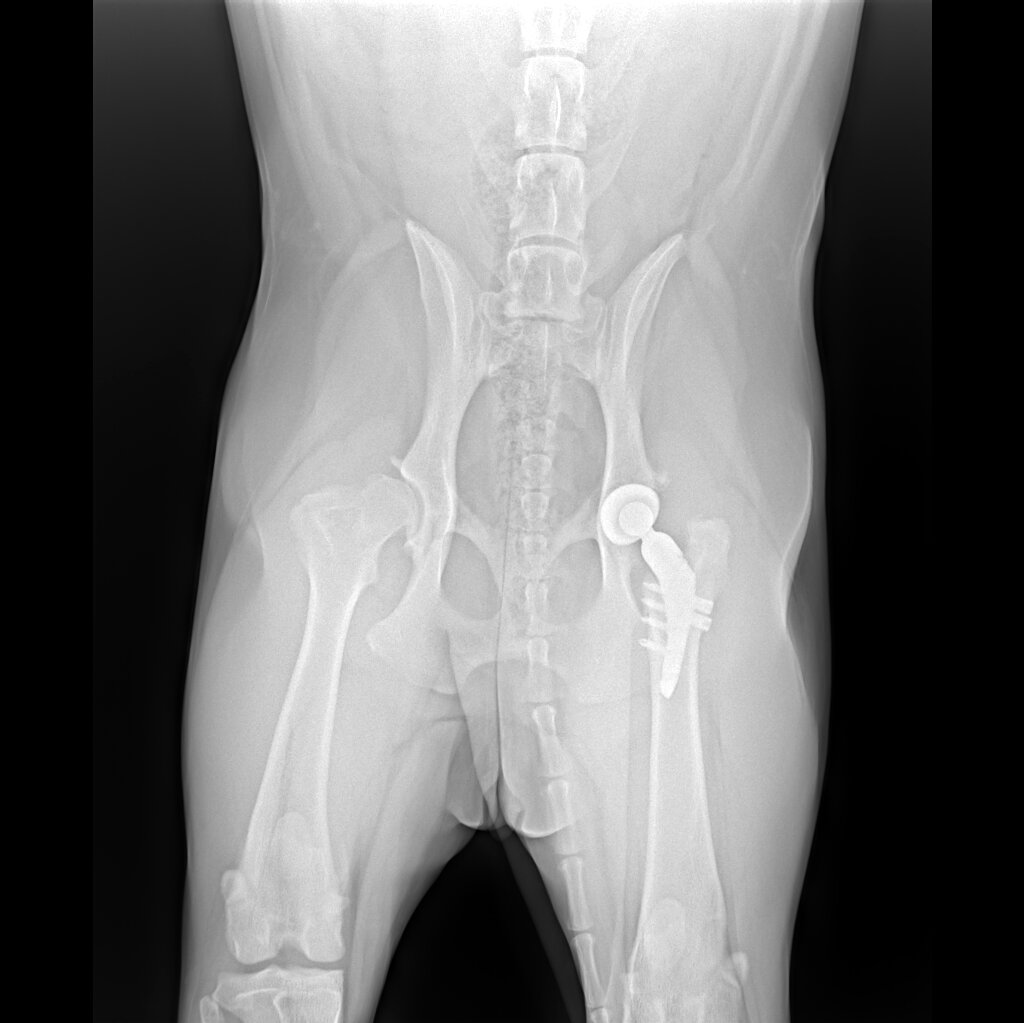

левая сторона - протез/правая сторона - разрушенный сустав, который под замену в 25м году.

на правой стороне снимка выше можно увидеть разрушенный сустав, где головка бедра явно не круглой формы, а вертлужной впадины как таковой вообще нет, сам сустав живет за счет мышечной массы, за что спасибо миопластике; в норме у собаки бедренная кость сидит полотно в тазовой кости, имеет ровные округлые формы. Протезированная сторона у нас может считаться здоровой. Да дорого (но как мы видим из расценок выше из протезирования вырисовывается разовая крупная трата, зато в перспективе экономия и долгие годы без болей), да сложная реабилитация, но если выбирать между страданиями пожизненными и благополучием собаки, по мне так выбор очевиден.